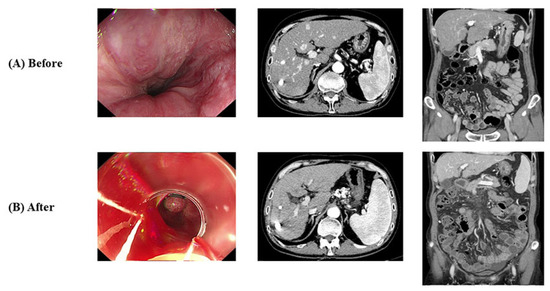

- Case 2